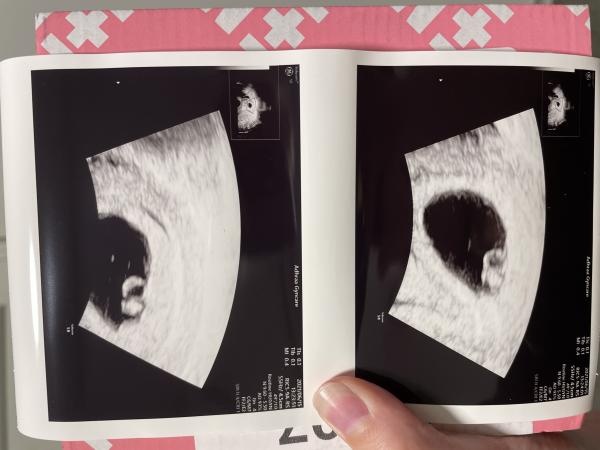

Var på vul idag 5+6 fick se ett litet hjärta slå. Trodde jag bara skulle få se en hinnsäck och ev en skugga av fostret.

Vecka 5+3 avstannade förra graviditeten så känns skönt att vara förbi den dagen men tänkte på att hade hen stannat så hade jag ju varit i v. 14 nu.